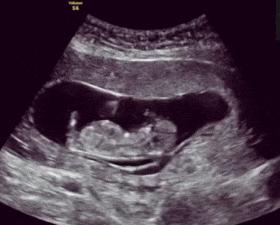

从28周起,医生会让孕妈在家注意胎动,数胎动是孕妈发现问题的方式,而解决问题是需要医生帮助的,所以,数胎动并不会非常复杂。